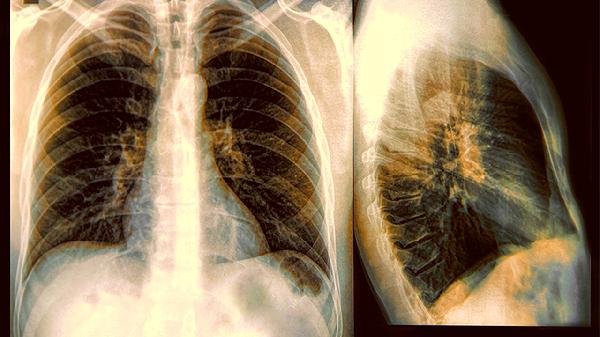

1.肺结节的基本概念

肺结节是指直径小于3厘米的肺部异常阴影,在CT影像上呈现为圆形或类圆形。就像相机拍到了模糊的小光斑,需要进一步对焦才能看清细节。